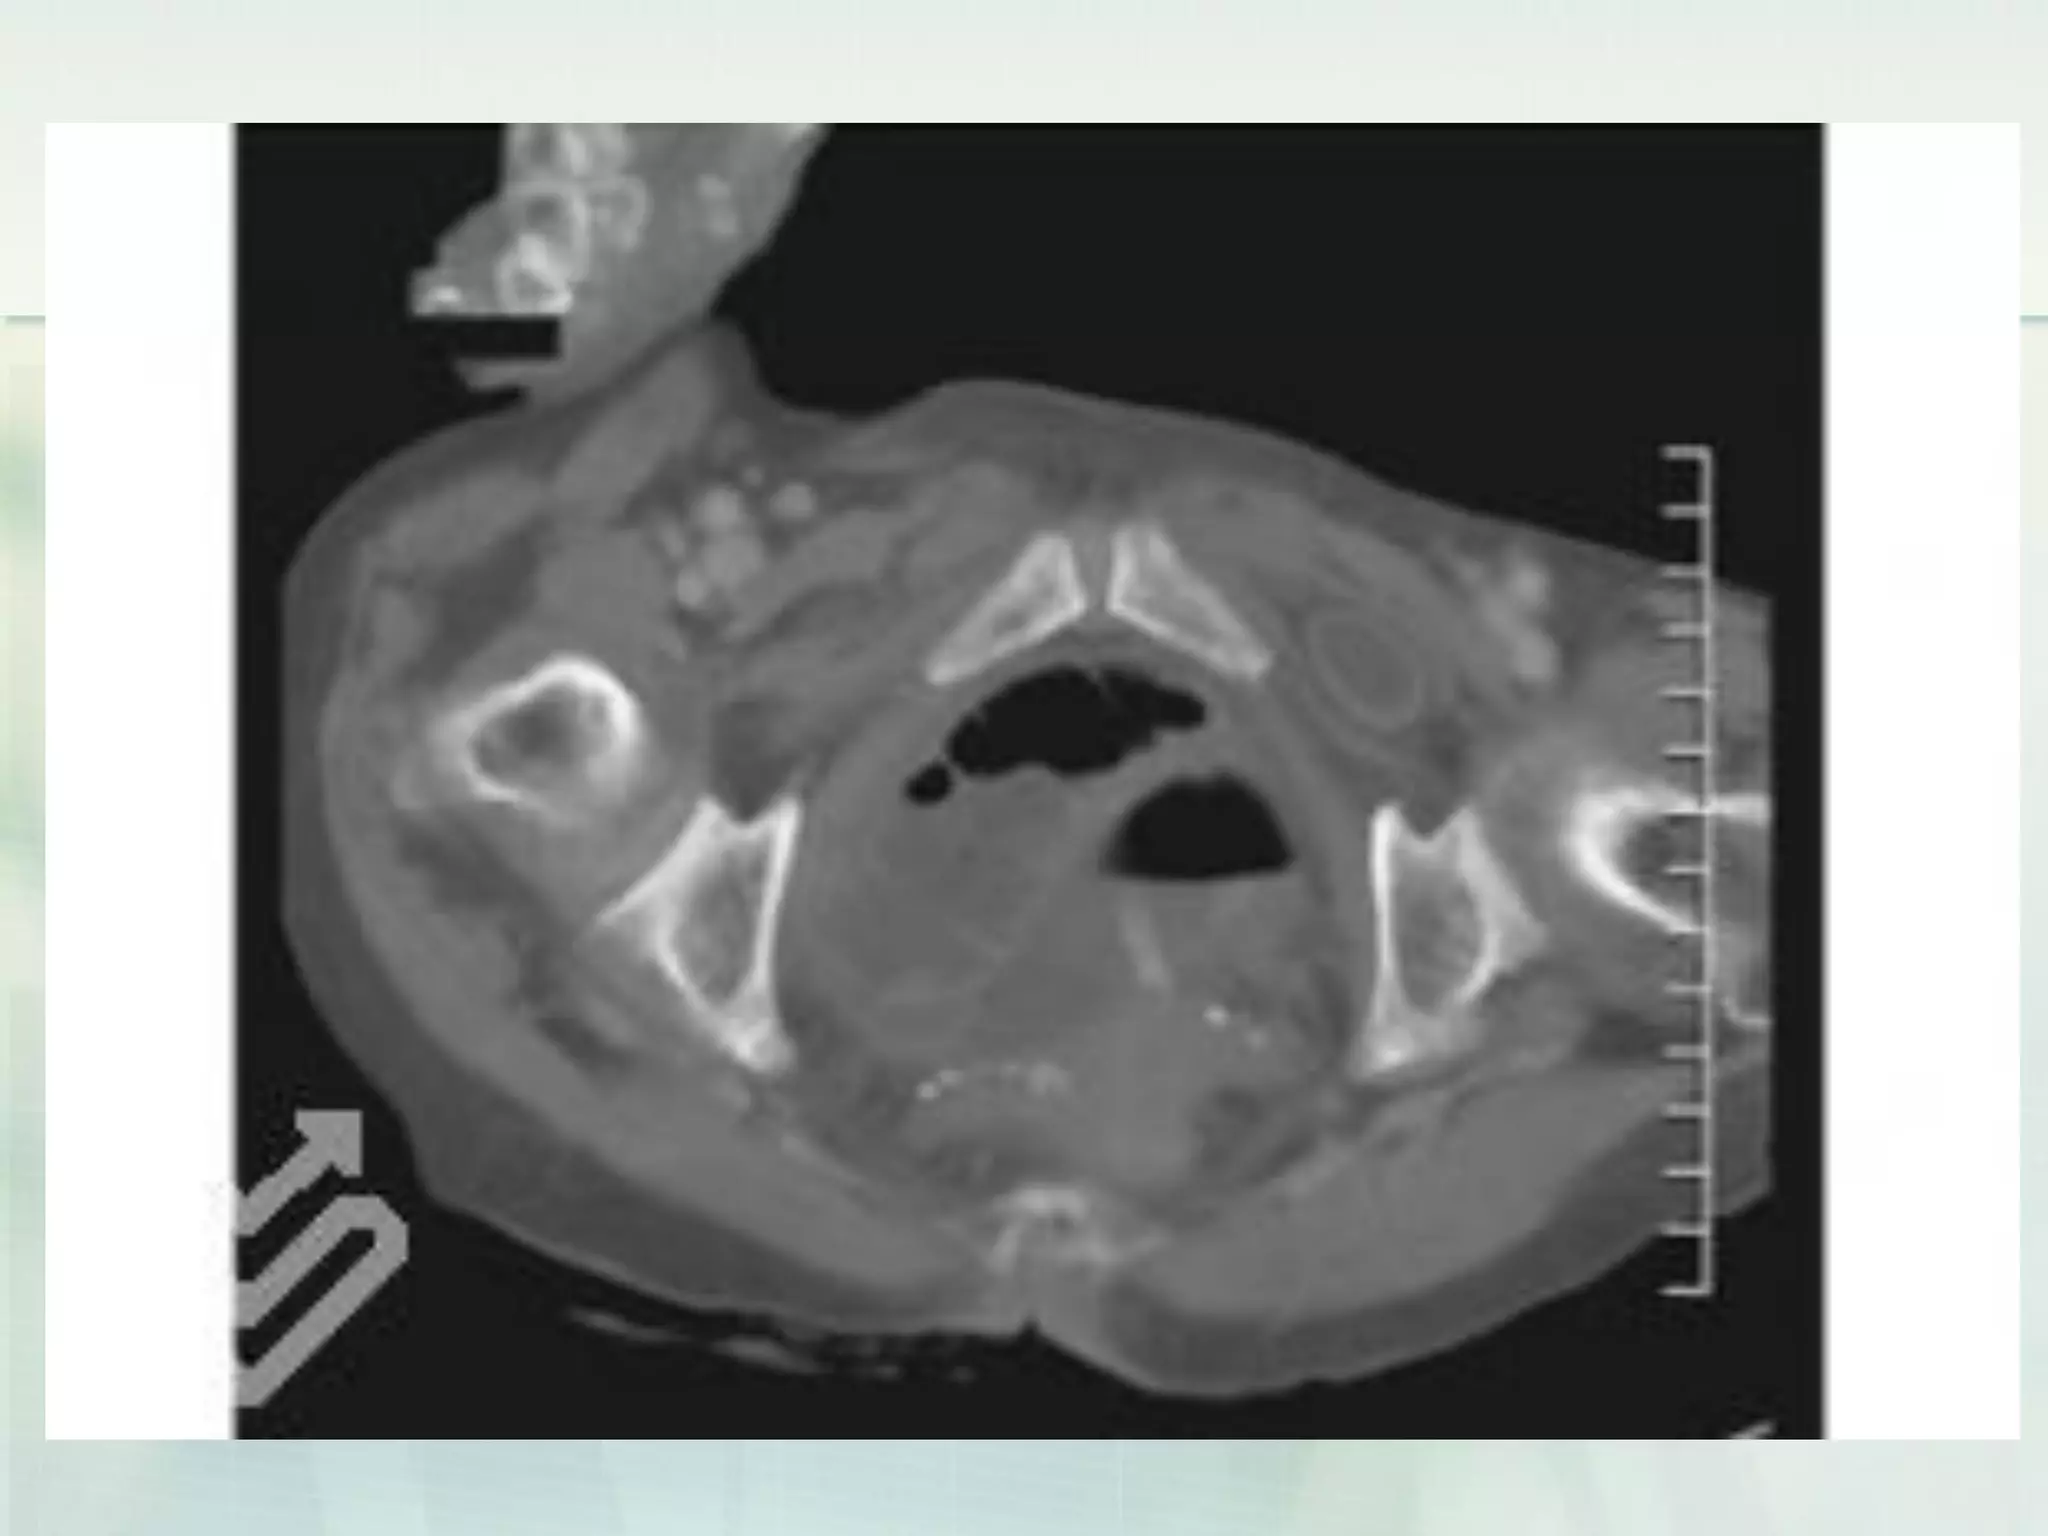

 Computed tomography (CT) is playing a

growing role in the diagnosis of intestinal

obstruction.

 Signs of obstruction by CT scan include

proximal dilatation with transition point and

closed-loop obstruction with a 'beak' sign.

 Small bowel strangulation can be shown as

circumferential thickening of the bowel wall,

increased small bowel attenuation,

pneumatosis, and 'target sign' secondary to

thickening.

CT scan of a small bowel

obstruction

Laboratory investigations (Small bowelobstruction)  Computed tomography (CT) is playing a growing role in the diagnosis of intestinal obstruction.  Signs of obstruction by CT scan include proximal dilatation with transition point and closed-loop obstruction with a 'beak' sign.  Small bowel strangulation can be shown as circumferential thickening of the bowel wall, increased small bowel attenuation, pneumatosis, and 'target sign' secondary to thickening.

• 28.

CT scan ofa small bowel obstruction